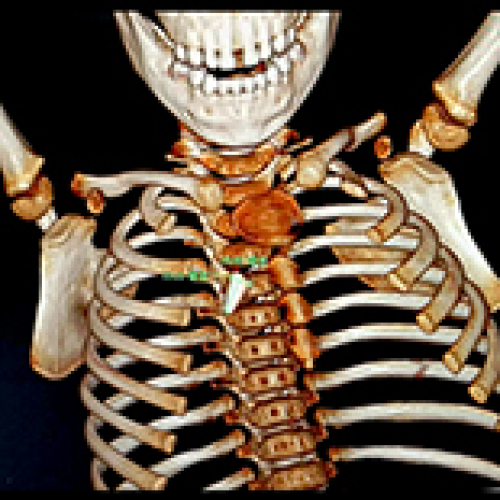

14 Nov 2022 : Clinical Research

Characteristics and Treatment of Pediatric Tracheobronchial Foreign Bodies: A Retrospective Analysis of 715 Cases

Shang Yan, Peng Jiang, Guowei Chen, Yongchao Chen, Hongguang Pan, Lan Li, Nan Zeng

DOI: 10.12659/MSM.937928

Med Sci Monit 2022; 28:e937928